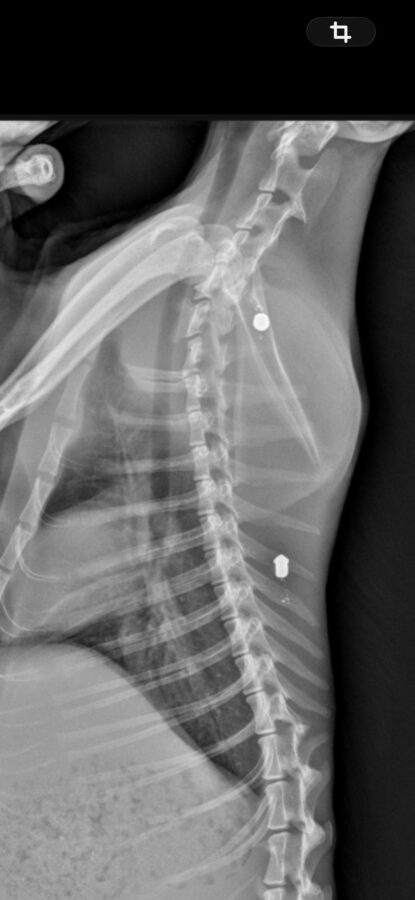

Las radiografías realizadas al animal confirmaron la presencia de dos proyectiles compatibles con perdigones, lo que apunta a un acto intencionado de violencia contra los animales

Las radiografías realizadas al animal confirmaron la presencia de dos proyectiles compatibles con perdigones, lo que apunta a un acto intencionado de violencia contra los animales. El caso ha sido hecho público por personas voluntarias dedicadas a la protección y cuidado de colonias felinas en Fraga, que alertan de la gravedad de lo ocurrido y de la vulnerabilidad de estos animales.